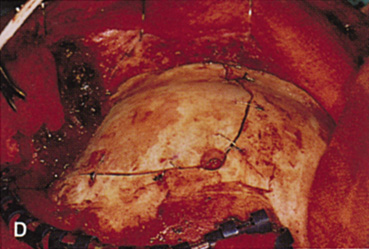

Fig. 14. A,B. Large intraorbital lymphangioma causing proptosis and optic nerve compression

over the superior orbit. The orbital mass is exposed in this fashion. D. The fronto-orbital bone flap is wired back in place after completion of

the procedure. E. Postoperative appearance of the patient. F. The postoperative CT scan shows complete removal of the lymphangioma. This

large and diffuse lesion would have been difficult to remove with

frontal bone, supraorbital rim, and orbital roof. After the dissection, the dura is closed and the frontal bone flap is plated

or wired back into position (see Fig. 14D). The orbital

roof is functionally restored with the replacement of the bone flap. The